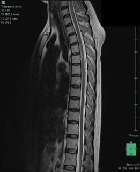

One-lung Ventilation in a Child with Hyper-IgE Syndrome

Arianna De Matteis*, Paolo Palma, Francesca Stoppa, Raffaele Badolato, Alessia Scarselli, Patrizia D’Argenio, Corrado Cecchetti, Renato Cutrera, Alessandro Inserra6, Nicola Pirozzi, Caterina Cancrini